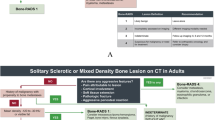

In Fig. 3, the study design is summarized in graphical form to facilitate comprehension, as recommended in the ARRIVE guidelines [14].